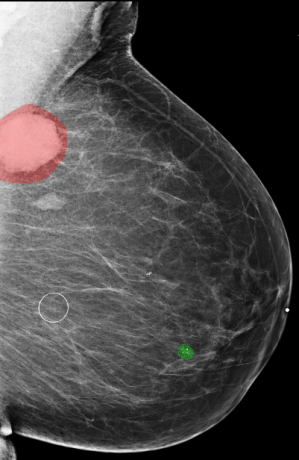

Traditional computer-aided detection (CAD) tools for mammography neither detected more breast cancers nor decreased the recall rates for additional imaging [10, 11]. Early studies used deep neural networks (DNNs) to assist radiologists interpreting screening mammograms by making predictions for cancer of each breast [12, 13, 14, 15, 16, 17, 18]. This task is frequently considered in literature. It can be viewed as breast-level classification, and models developed accordingly have shown comparable performance to radiologists [16, 17, 18]. However, these models suffer from performance degradation when evaluated on a population only containing exams which lead to biopsies, without healthy breasts as negative cases [16]. Meanwhile, models built for the breast-level classification task cannot provide independent risk estimations for multiple areas of interests appearing in the same breast. It is common to encounter cases with multiple findings [19]. For example, multiple bilateral circumscribed breast masses are detected in approximately 1.7% of routine screening mammograms [20]. In the NYU Breast Cancer Screening Dataset [21], a representative sample of screening mammograms from 2010 to 2017, there are 7.45% images with more than one annotated lesions, and 25.75% of these images have lesions of different categories. Some examples are shown in Figure 1. In light of this, the previously proposed models for breast-level classification are difficult to use for the goal of reducing unnecessary biopsies.

![]() |

| a | b |